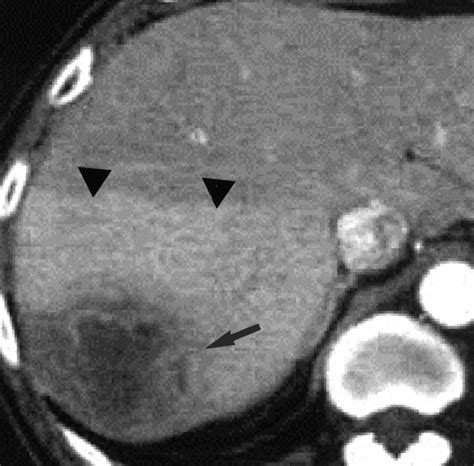

Diagnosing a liver abscess involves a combination of medical history, physical examination, and diagnostic tests. Imaging studies such as ultrasound, CT scans, and MRI are commonly used to visualize the abscess. Blood tests can help identify the underlying infection, and sometimes, a sample of the abscess fluid may be taken for culture and sensitivity testing.